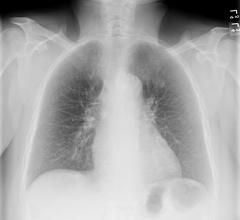

December 19, 2012 — Three studies presented at the 98th annual meeting of the Radiological Society of North America (RSNA) in November reported that using bone suppression and computer-aided detection (CAD) software significantly improves the detection of lung nodules on chest X-ray images.

September 14, 2012 — A radiologist’s ability to detect pneumonia early — so it can be treated quickly — is improved by Riverain Technologies software that suppresses the ribs and clavicles on a chest X-ray, suggests new research published online by European Radiology.